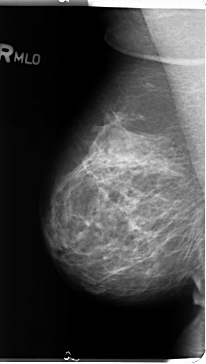

B_3125_1.RIGHT_MLO

RIGHT_MLO LINES 4720 PIXELS_PER_LINE 2672 BITS_PER_PIXEL 12 RESOLUTION 50 NON_OVERLAY